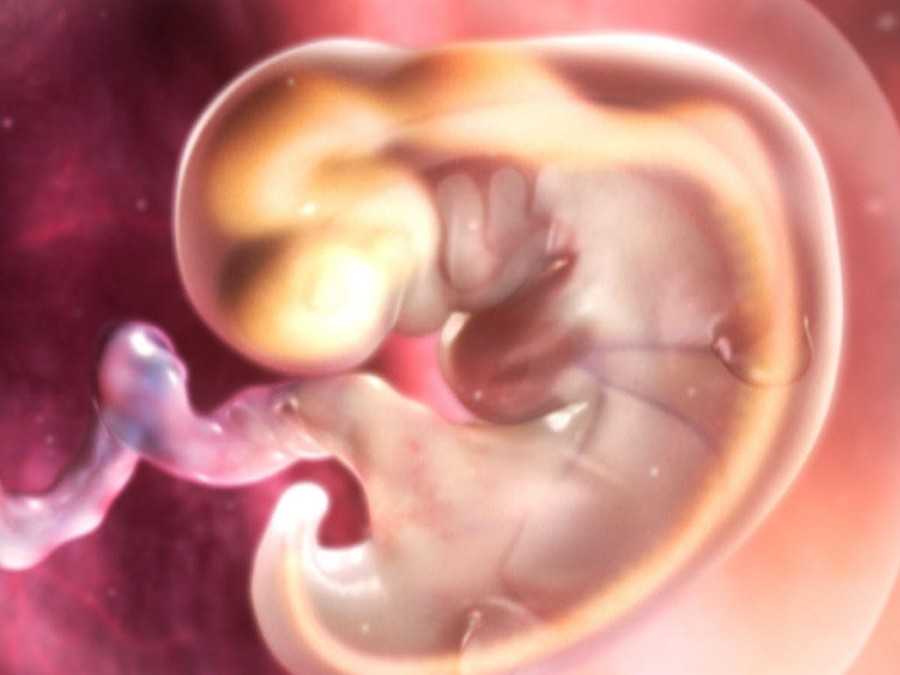

Вот так выглядит твой малыш на 9 неделе (фото плода)

Фото плода и живота матери на сроке 9 недель

Как выглядит эмбрион на 9 неделе? Ваш кроха еще подрос. У него уже начинает формироваться личико, удлиняются конечности, появляются пальчики. Именно на данном этапе ребенок прогрессирует и становится не эмбрионом, а плодом, поскольку большой палец на руке разворачивается так, что прижимается к ладони с внутренней стороны (противостоящий палец).

Уже можно заметить пуповину. И именно с этой недели ваш малыш начинает развиваться быстрее вдвое.